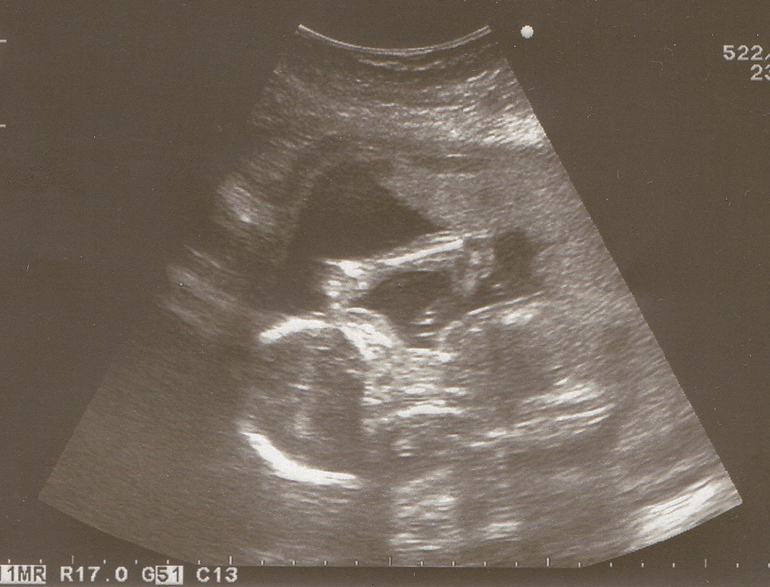

Пока у нас все хорошо. На узи в 20 недель весили мы уже 350 гр (как узистка сказала 3,5 плитки шоколада=))))). Нам даже сделали фото на память. Правда когда фоткать стали, повернулся он к нам попой=))). А до этого мне показывали и личико его, даже рассмотрела губки, глаза, носик. Люблю его безумно.